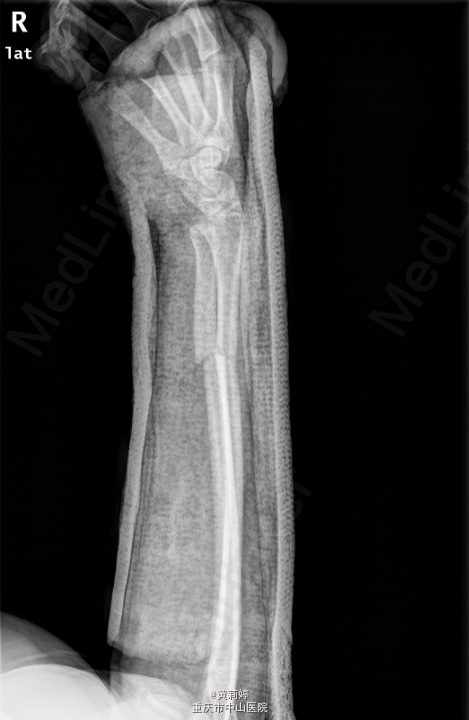

患者,男,17岁,因“摔伤致右侧前臂及腕部胀痛伴活动受限1天”入院。

右前臂石膏托固定,右前臂肿胀,畸形,压痛明显,右腕活动障碍,手指血运好,活动可,其余肢体无明显异常,神经系统检查无殊。我院右尺桡骨正侧位片示:右尺桡骨远段骨折、石膏外固定改变。我院右腕关节CT示:右尺桡骨远段骨折、石膏外固定术后。